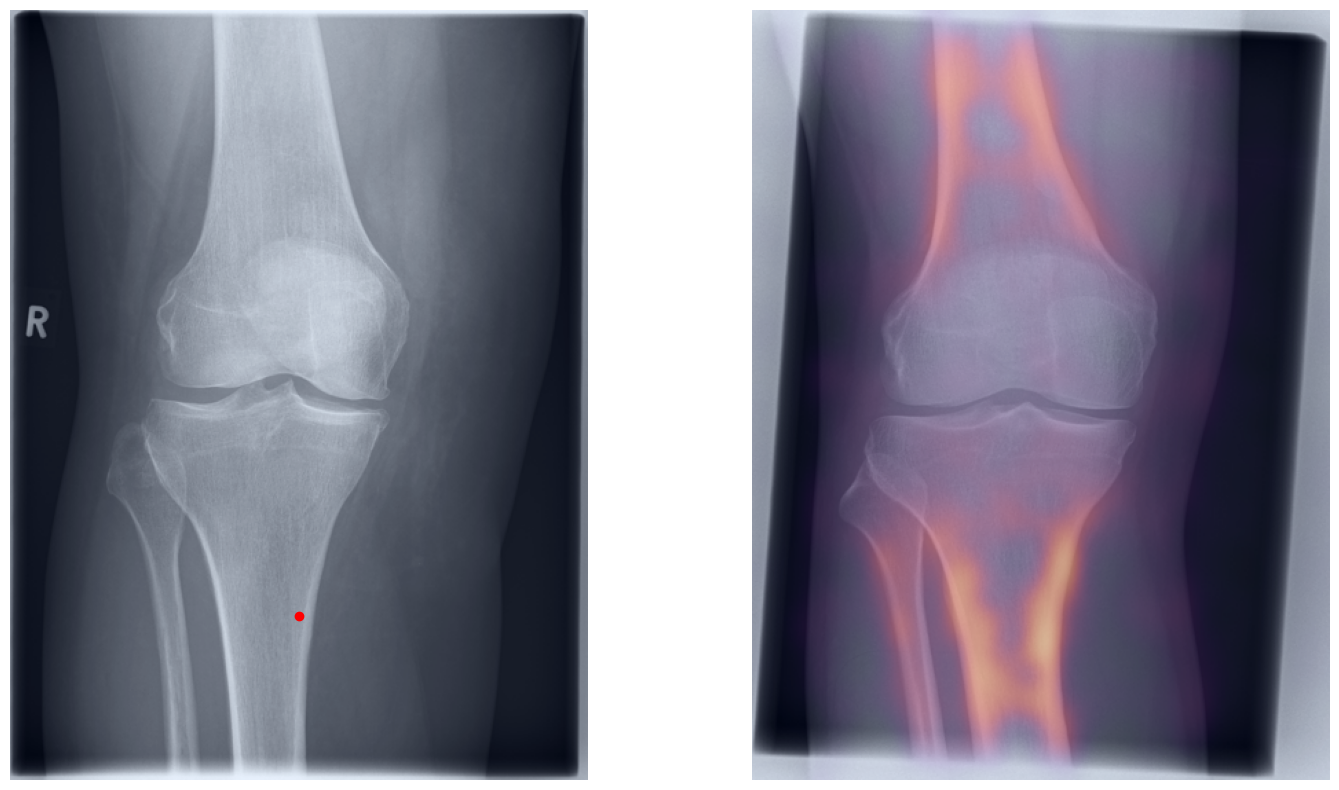

Artificial intelligence (AI) has shown great potential in assisting radiologists with musculoskeletal (MSK) assessments across various anatomical regions1,2,3,4. However, most existing tools are narrowly tailored for specific anatomies or rely on segmentation-based methods as a basis. To address these limitations, we propose a versatile and generalist AI-based approach for landmarks matching. In contrast to typical generalist landmark matching approaches that depend on automatically identified, optimally descriptive landmarks5,6,7, our use-case has to be based on manually selected landmarks tailored for MSK measurements. As these landmarks are potentially subotimal for precise matching, we employ an AI-based method8 that first performs multi-scale dense image matching between the reference and target images independently of the landmarks. The AI uses a combination of transformer and convolutional neural networks to establish a multi-resolution descriptive feature representation of each position within the images, allowing to define correspondences between the reference and target images. In a subsequent step, landmark positions are transferred to the target image based on these correspondences, with the determination of final locations benefiting from the redundancy of the dense matching. This enables robust automation of landmark matching from a reference patient across an entire cohort of target patients. The approach is anatomy-agnostic, enabling the use of the same backbone model for a wide range of anatomical regions and MSK measurements. For more detailed information we refer to our paper.

Once a correspondence between the reference and target radiographs is established, landmark matching can be performed in real-time. This process enables the alignment of individual points and allows for the definition of a predefined set of landmarks that can be mapped onto the target patient. These predefined landmarks can be customized for the automated calculation of specific measurements, which, once defined on a reference patient, can be consistently and automatically transferred to any radiograph within the target cohort.

The process of establishing a dense match between two images relies on abstract feature representations for each position in both the reference and target images. To better understand which information is encoded by the AI, we examined the feature similarities between a specific position within the reference image and the entire target image. Our findings show that the AI captures both semantic and texture features. The matching process utilizes this encoded information, along with precise positional data, to create a reliable mapping between the images.